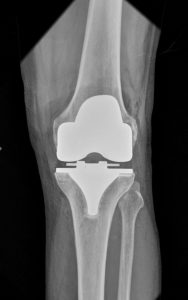

O ROSA Knee System auxilia os cirurgiões na realização da Artroplastia Total do Joelho (ATJ) com recursos para auxiliar nas ressecções ósseas, além de avaliar o estado dos tecidos moles para facilitar o posicionamento do implante no intraoperatório.